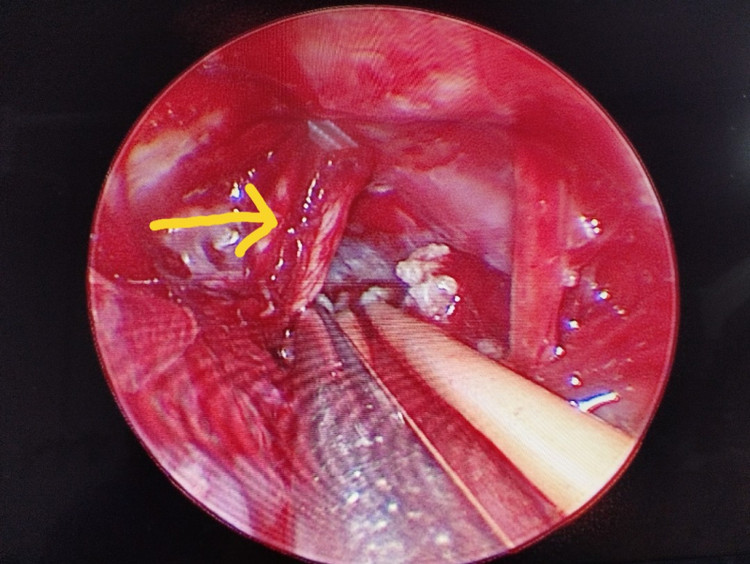

Dưới sự hỗ trợ của hệ thống phẫu thuật vi phẫu và nội soi hỗ trợ, Ekip phẫu thuật của Ths.BS Giang Lộc Anh (Khoa Ngoại – Thần kinh lồng ngực, Bệnh viện Bãi Cháy) đã tiến hành mở xương sọ sau xoang sigma, lấy u tối đa, giải ép xung đột mạch máu - thần kinh V. Ca phẫu thuật diễn ra an toàn, đảm bảo cầm máu tốt và bảo tồn cấu trúc não lành và các dây thần kinh quan trọng. Sau 7 ngày, bệnh nhân phục hồi tốt, giảm đau rõ rệt, không ghi nhận biến chứng và được xuất viện.

Xung đột mạch máu và thần kinh V trên hệ thống nội soi

Hiện nay, với sự hỗ trợ đắc lực của các trang thiết bị hiện đại như hệ thống vi phẫu, hệ thống nội soi, phẫu thuật viên có thể quan sát phẫu trường vùng góc cầu – tiểu não, vùng gần thân não, các vị trí xung đột mạch máu – thần kinh dưới nhiều góc độ hơn, rõ ràng hơn.